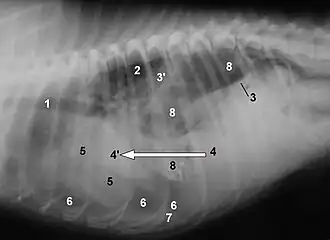

La rotura diafragmática es una complicación común y bien conocida de los traumatismos abdominales contusos en perros y gatos. Los órganos que se hernian en la cavidad pleural vienen determinados por la localización de la rotura. Lo más habitual es que se trate de desgarros circunferenciales que se producen en la unión del diafragma y la costilla. En estos casos, los órganos que se hernian pueden ser el hígado, el intestino delgado, el estómago, el bazo, el epiplón o el útero. Los desgarros dorsales son infrecuentes y pueden provocar la herniación de un riñón hacia el tórax. Los síntomas incluyen dificultad para respirar, vómitos, colapso y ausencia de órganos palpables en el abdomen. Los síntomas pueden empeorar rápidamente y ser letales, sobre todo en caso de hemorragia grave, contusión cardíaca o estrangulamiento del intestino herniado. También es posible que sólo haya signos sutiles y la afección sólo se detecte incidentalmente meses o años después de la lesión durante una exploración médica.[15]